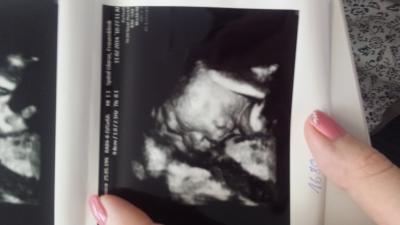

Huhu Mädels, War heute zur 3..grossen vu &522; Dem kleinen geht es super. 2068 Gramm und laut Ultraschall bei 33+4. Bin aber eigentlich erst 31+6. Sonst ist alles toll und meine schmerzen sind viiiiiel besser geworden. Als Anhang ein 3 d Bild hihi so süß er macht ein Kuss mund &525;

Bild zu zurück vom Frauenarzt - Forum für April - Mamis

Ui, da kriegst du ja einen kräftigen kleinen Mann. Schön, dass alles i.O. ist. Und so ein schönes Bild! Hätte gerne auch noch eines, aber meine Maus schaut immer immer immer mit dem Gesicht nach hinten, sodass kein gutes Bild möglich ist.